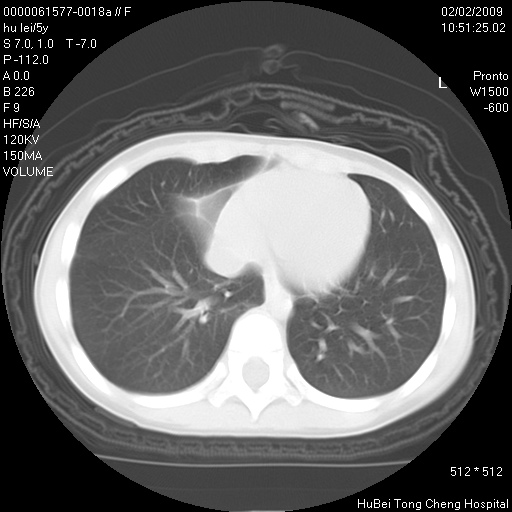

标题: PED1732:M5Y,右肺囊性占位!

患者:男,5。无明显不适,拍胸片考虑右肺囊肿。

行ct扫描,图象如下:

病灶与前胸壁和右上纵隔、叶间裂界限不清,病灶前缘及内侧缘看不到正常的肺组织,不能排除包裹性积液。